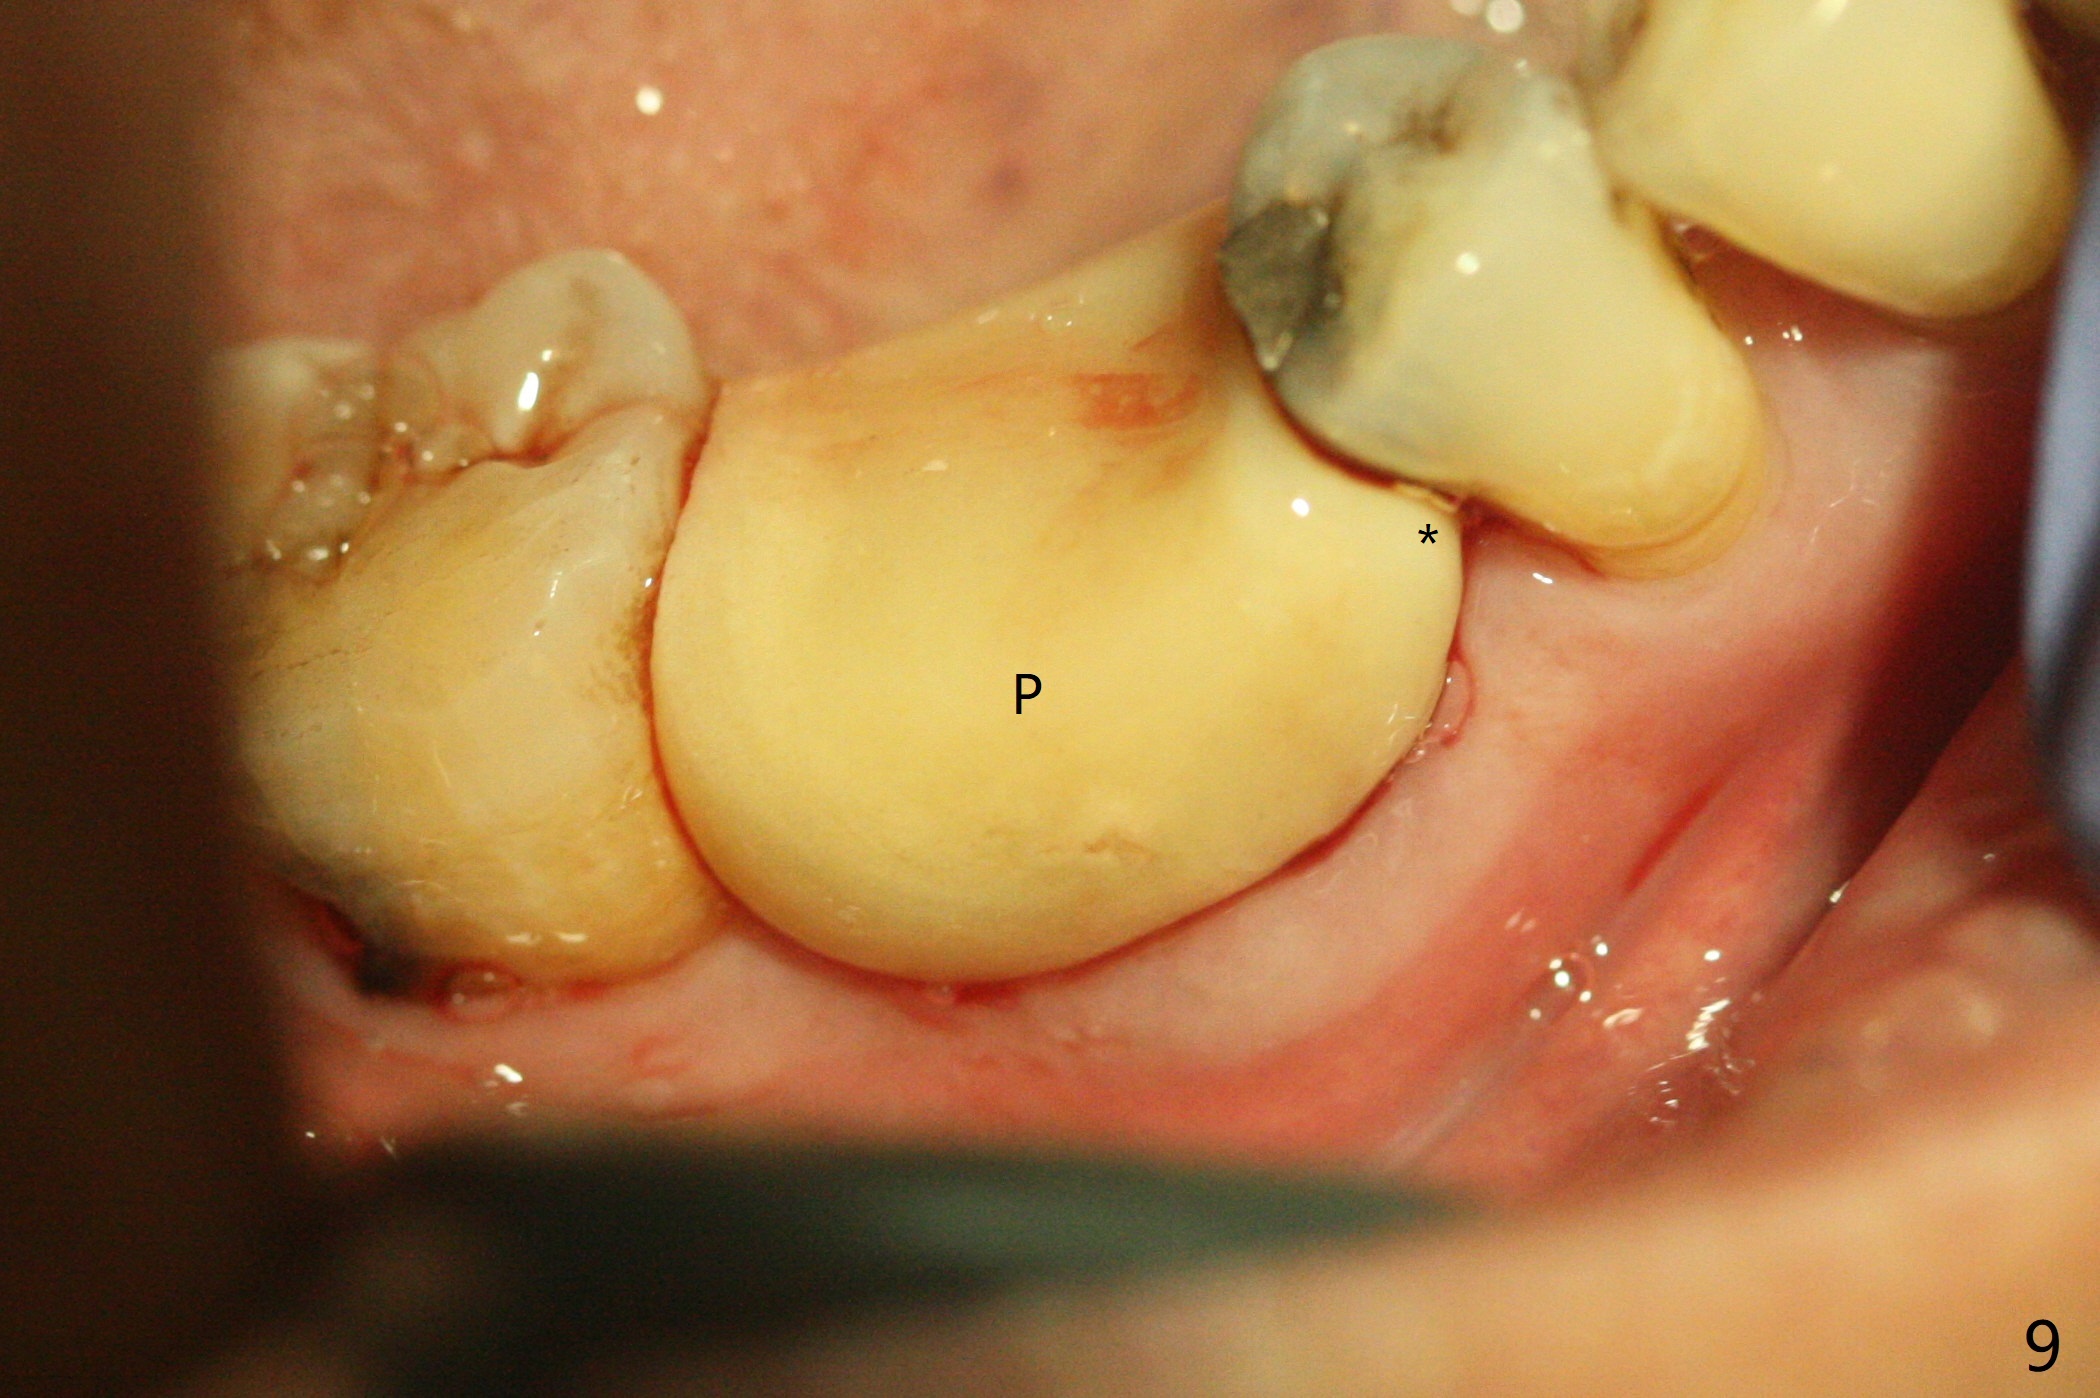

As planned, the crown of the tooth #30 with lingual (Fig.1 L) caries is removed and flattened with surgical handpiece so that the guide is able to be seated without interference. The osteotomy by 10.5 mm offset bone trimmer is lingual (Fig.2 white circle; due to in part the lingual caries and in part design error); in order to let the osteotomy to bounce back buccal, the part of the buccal roots are removed by surgical bur (arrows). The initial osteotomy by 2.2 mm drill is in the middle of the septum (Fig.3). After the last drill (3.5x11.5), the remaining roots are easily removed with proximators; a 4x11 mm dummy implant is placed with low stability and supracrestal lingual (Fig.4). Therefore a 4.5x9 mm final implant is placed with low torque. Following 4x11.5 mm drill, the torque increases to 20 Ncm. With insertion of healing screw, sticky bone (Fig.4 *: .5-1 mm cortical/cancellous allograft) is heavily packed around the implant (arrow), which apparently allows removal of the healing screw and placement of a 6x5.7(3) mm pair abutment without loosening the underlying implant. More bone graft is placed (Fig.6), followed by 2 pieces of PRF membranes. Although the implant is slightly buccally placed (Fig.7, due to over-removal of the buccal root, Fig.2 arrows), it is placed in the septum (Fig.8 S). To further compensate for the low implant stability, setting acrylic is applied in the edentulous area, particularly into the undercuts of the neighboring teeth (Fig.9 *) and around the abutment. The lingual margin of the acrylic dressing is extended (Fig.10 arrow) to cover the soft tissue defect associated with the lingual caries. As compared to the design (4x10 mm, Fig.11), the implant (4.5x9 mm, Fig.12) is placed buccal and ~ 2 mm deeper, reducing the chance of periimplantitis. The acrylic dressing is in place, but has mobility. The gingiva is healthy 2 weeks postop. The dressing is removed 1 month postop; the socket heals around the abutment buccal (Fig.13) and lingual (Fig.14). In spite of the immediate provisional, the abutment margin is substantially subgingival mesial 4 months postop, extremely difficult to take impression. A smaller diameter and longer cuff abutment is placed (Fig.15). The lingual gingiva heals normal 5 months postop, immediately before cementation (Fig.16).